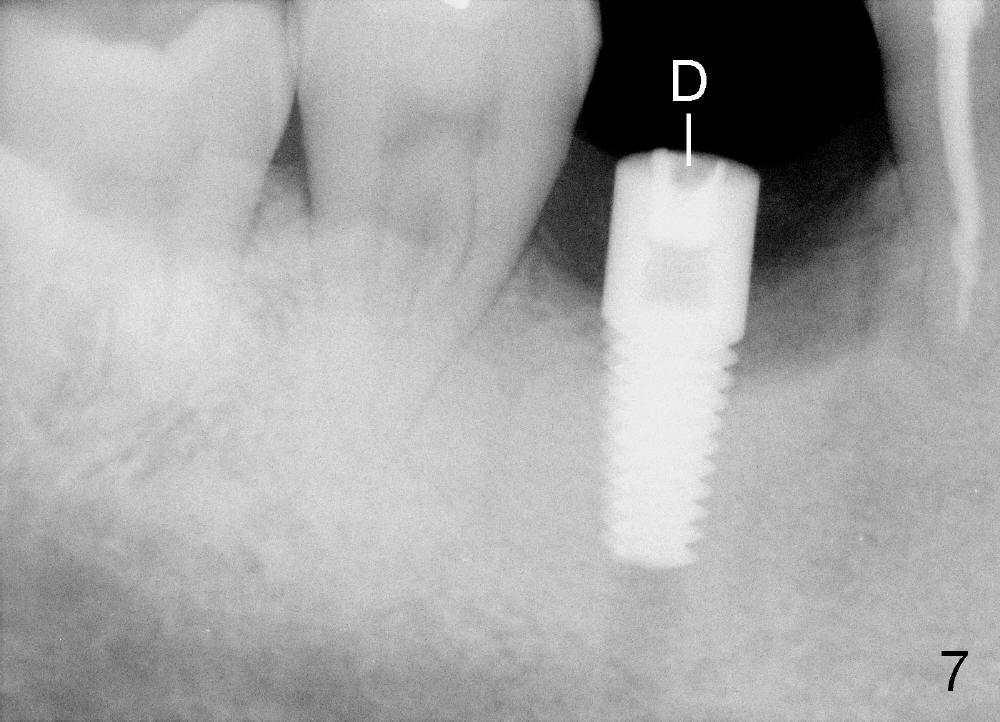

A 46-year-old man has severe periodontitis. The tooth #30 is complicated by incomplete root canal therapy (Fig.1,2). Three months after extraction (Fig.3-5: N: inferior alveolar canal), a 5x14 Tatum tapered implant is placed (Fig.6,7). The problem is that an implant driver is fractured (D in Fig.7), while the implant is being torqued. It takes time and effort to remove the fractured driver, but the implant is solid. The healing screw is placed without difficulty (Fig.8). Since the implant is placed lower than the lingual gingiva (L in Fig.9), a healing cuff is placed 1.5 months after implant placement (Fig. 10 and 11: C) to push the lingual gingiva down. The X-ray appears to show lower bone density around the implant (bone necrosis?), although the implant has no mobility at all. Since the implant is so solid, can we load it, two months after surgery? The lingual gingiva is now lower than the healing cuff (not shown). CT is scheduled to be taken tomorrow. Thanks.